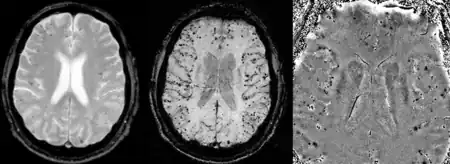

Cerebral amyloid angiopathy can be presented with lobar intracerebral hemorrhage or microbleeds in the brain. The bleeding usually occurs on the surfaces of the brain in contrast with intracranial haemorrhage due to high blood pressure which occurs in deep locations of the brain such as basal ganglia and pons. In lobar intracerebral bleed, computed tomography (CT) scan would show hyperdense haemorrhage area and hypodense odema around the haemorrhagic site.[24]

MRI sequence of gradient echo and susceptibility weighted imaging (SWI) are useful in detecting microbleeds and deposition of iron on the brain cortex (cortical superficial siderosis).[24] Other MRI indicators of CAA include white matter hyperintensities and cortical thinning.[30]